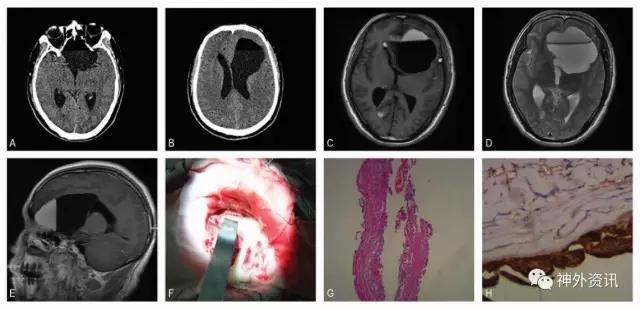

入院查体:T:38.3℃,昏睡,颈颈强直,左眼对光反射迟钝,余查体欠配合。头颅CT提示:鞍上池至左侧脑室前角形状不规则低密度占位,大小约6.7cm×6.9cm×5.5cm;病灶内可见液平,上层液体CT值约为-110,下层CT值约为+15(图1A,B)。头颅MRI检查提示同部位囊性病变,T1相呈下层低信号、上层高信号,T2相呈稍高至高信号;另,右侧脑室前角、脑沟内可见多发病灶,T1、T2相均呈高信号(图1C-E)。患者影像诊断尚不明确,为排除颅内转移瘤,遂进一步检测其血清肿瘤标志物提示:CA-125、CA-242、CEA均升高,CA-199升高尤其显著(12,000U/ml,正常范围0-37U/ml)。

图1. 该患者影像及病理资料。术前CT (A, B)提示颅内形状不规则低密度占位,自鞍上池延伸至左侧脑室前角。病灶内可见液平。磁共振(C-E)显示双侧脑室前角、脑沟内多发异常信号影;T1加权(C)可见左侧脑室前角显示下层低信号、上层高信号的病灶主体,T2加权(D)可见稍高及高信号病灶,强化不明显(E)。术中见肿瘤呈囊性,囊内为脂质样内容物,囊壁HE染色(G)提示复层扁平上皮,可见结缔组织附着。免疫组化(H)示CA-199强染色。

进一步追问病史,并完善胸腹部CT,以排除其他部位导致CA-199升高的常见癌性和非癌性疾病;相关检查均未见明显异常。该患者诊断考虑颅内囊性病变伴破裂。患者有明显颅高压症状,遂行开颅病变切除术。术中可见病变为囊性,内含黄色脂质样物质(图1F),吸除肿瘤内容物并予囊腔反复冲洗,囊肿包膜予近全切除。术后持续腰大池置管引流辅助廓清脑脊液内残余囊肿内容物。术后病理证实为颅内表皮样囊肿(图1G)。免疫组化显示CA-199染色强阳性(图1H),CA-125、CEA中等强度染色,CA-242阴性。术后复查MRI显示脂质样物质基本清除(图2A,B),术后第10天患者血清肿瘤标志物水平仍处于极高水平(图2K)。